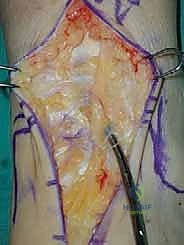

3. إزالة النتوءات العظمية وتحضير المفصل (Debridement)

بمجرد كشف المفصل، يقوم الجراح بإزالة الغشاء الزلالي الملتهب والزوائد العظمية (Osteophytes) التي تعيق الحركة. هذه الخطوة ضرورية لاستعادة المعالم التشريحية الطبيعية قبل إجراء القطع العظمي.